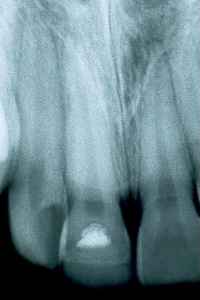

970818

Sekundärdentinbildning med tydliga gränser mellan Calxyl fosfatcement och komposit.